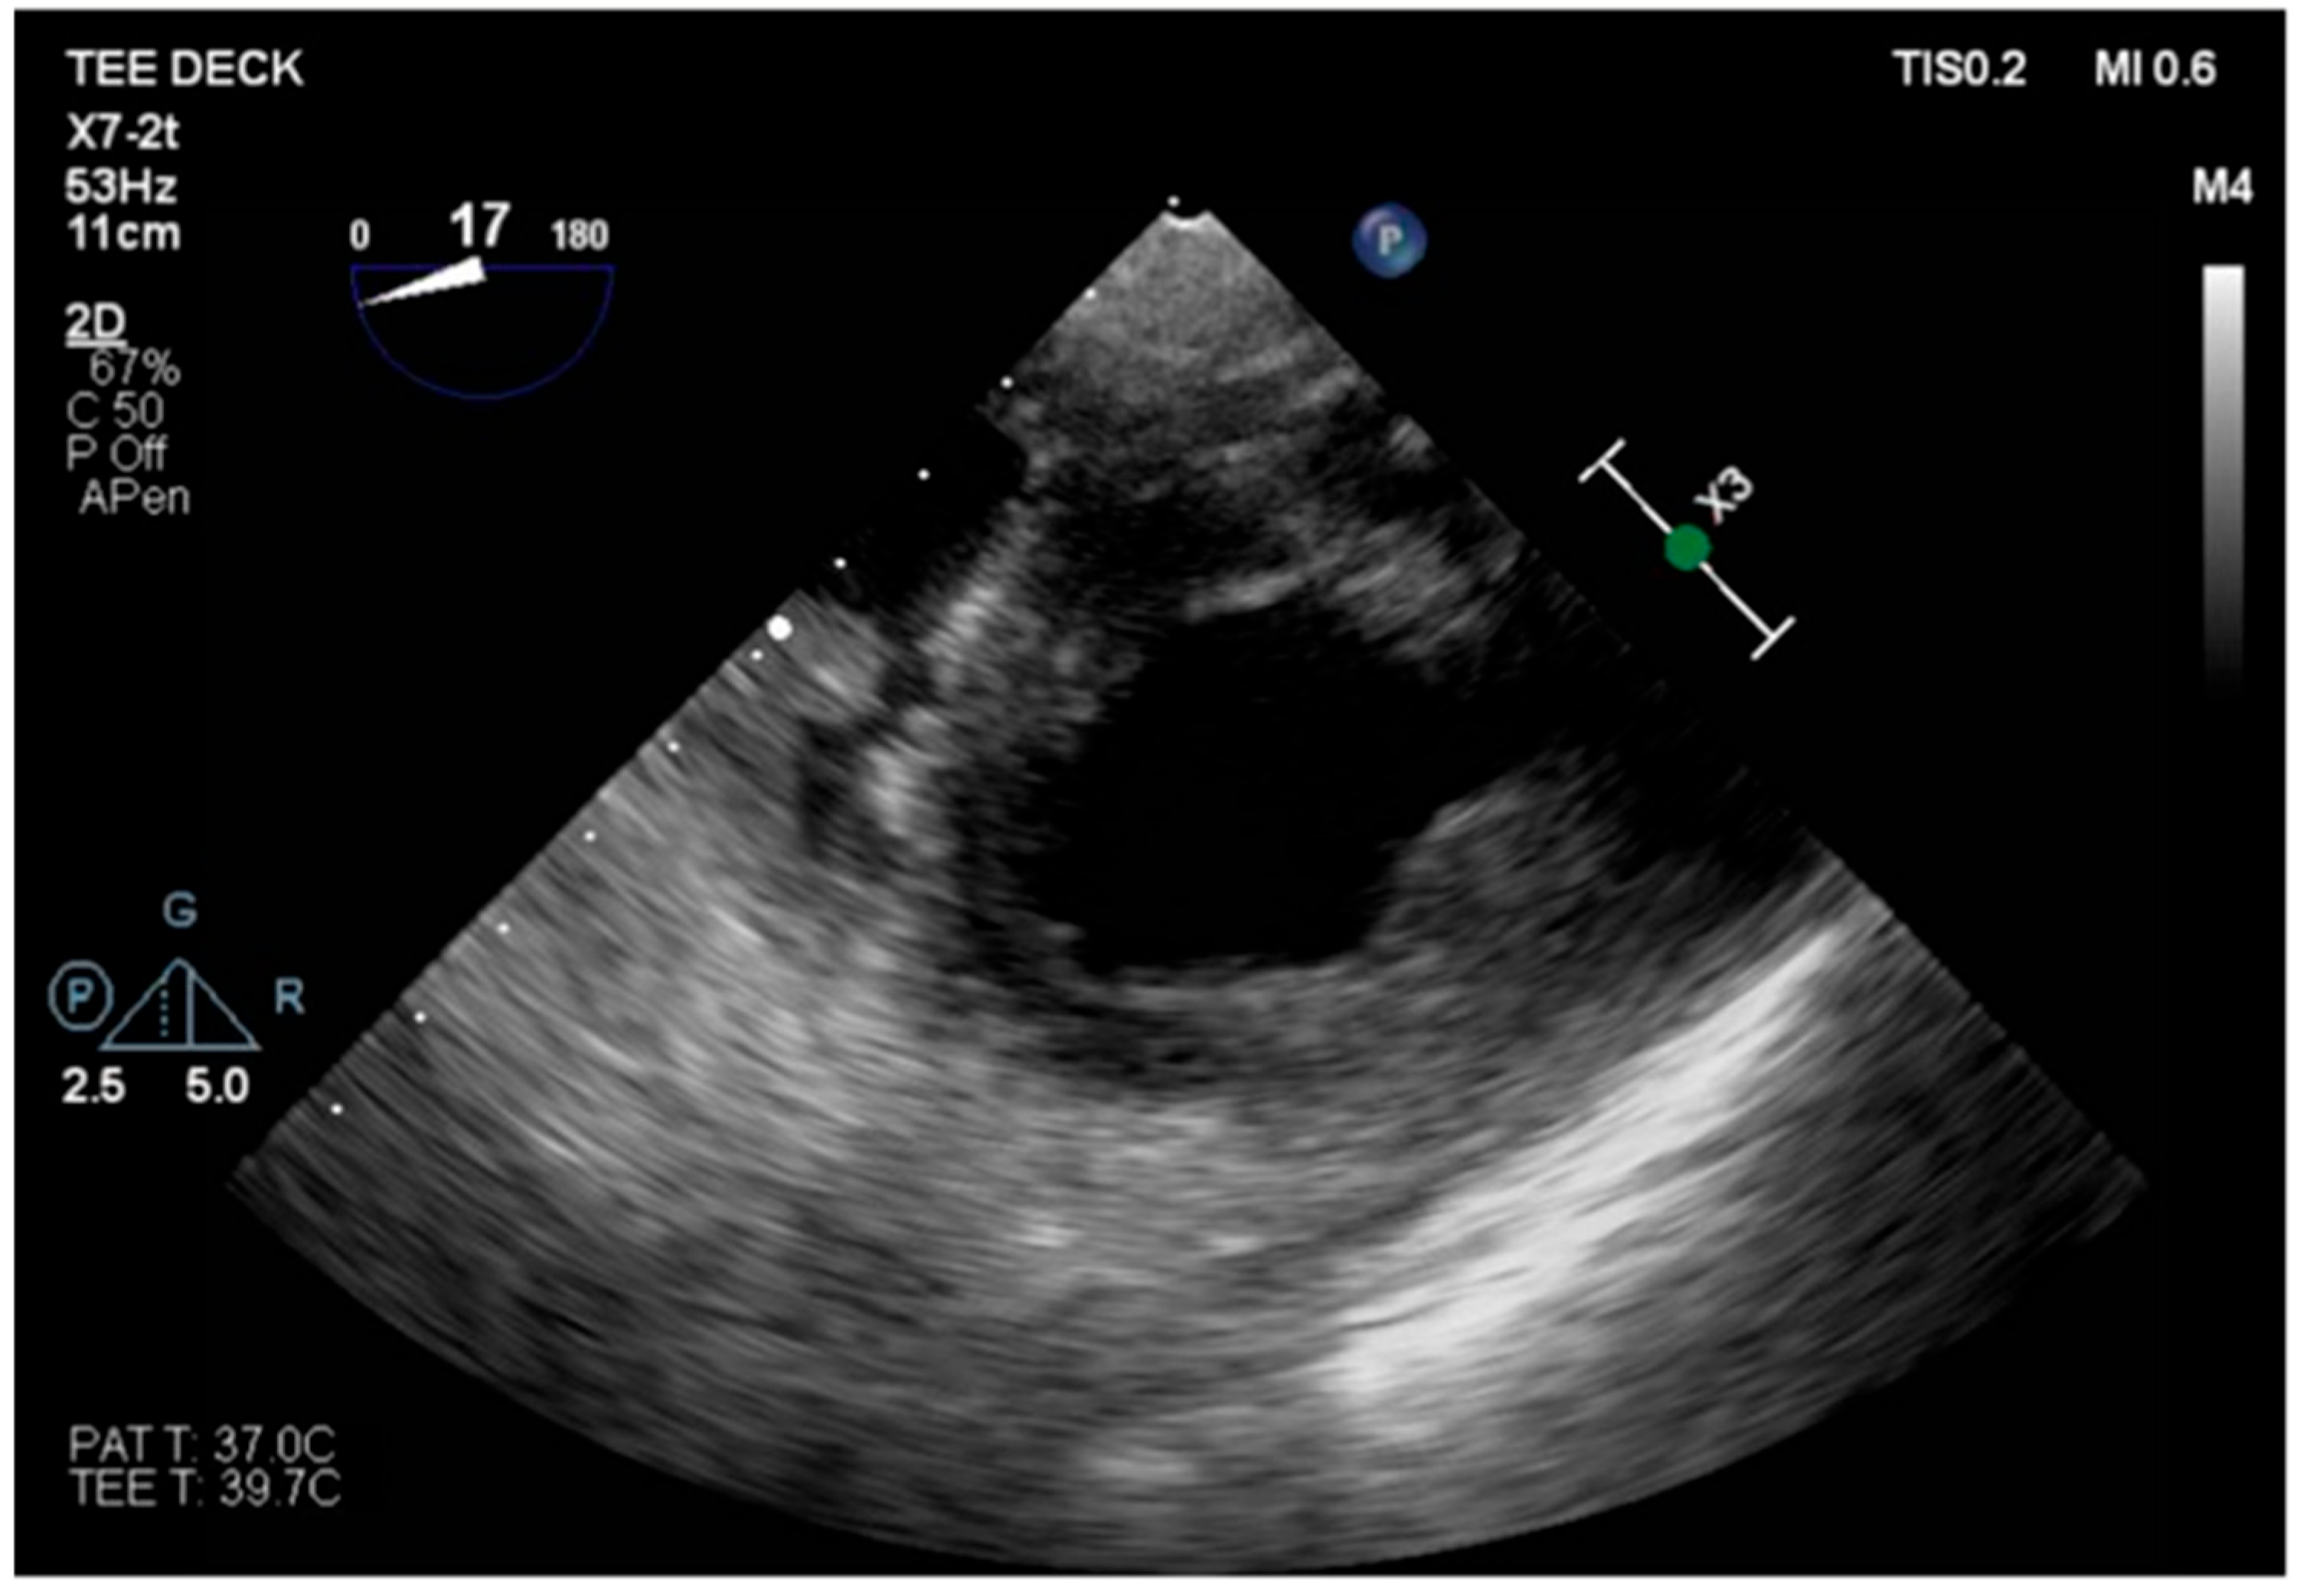

We describe a case of a 75-year-old woman affected by a post-myocardial-infarction ventricular septal defect (VSD) and a left-ventricle (LV) apical aneurysm. The patient underwent surgery for VSD closure and aneurysm exclusion. The patient had a STEMI (ST-elevation myocardial infarction), with evidence of occlusion of the anterior interventricular artery, for which thrombus aspiration and stenting of the left coronary artery and proximal anterior interventricular artery was performed. Then, she developed cardiogenic shock with pulmonary edema and thus required the support of an IABP (intra-aortic balloon pump) of C-PAP and levosimendan in continuous infusion for 24 h. Seven days after the event, a large post-infarct VSD at the apical level with a left–right shunt occurred. She was therefore transported from the spoke center to our hospital and underwent surgical treatment, namely, post-infarct VSD closure and exclusion of a left ventricular aneurysm. The intra-operative transesophageal echocardiography showed concentric LV remodeling, slight dilatation, LVEF 28% (Figure 1), and akinesia of the mid-apical segments in toto with aneurysmal evolution (Figure 2).

Figure 1. Mid-esophageal four-chamber view.